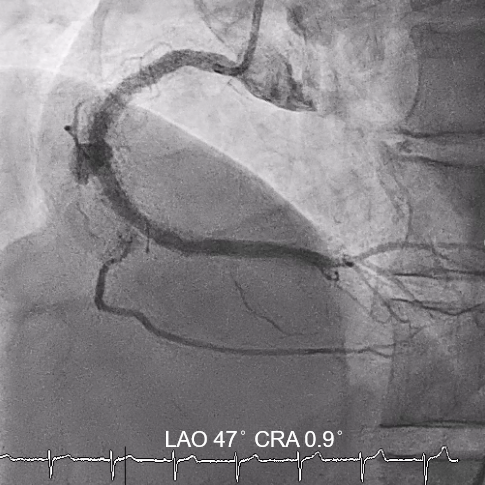

Subsequent coronary angiography identified a pseudoaneurysm in the right coronary artery (RCA), without any evidence of extravasation.

In this coronary catheterization procedure, a guidewire was used to cross the lesion and advanced to the posterolateral branch (PL). An intravascular ultrasound (IVUS) examination was conducted, revealing a pseudoaneurysm in the mid-right coronary artery (m-RCA). To cover the pseudoaneurysm, a 3.5 x 16 mm cover stent was deployed in the m-RCA at a pressure of 16-18 atmospheres for 15-20 seconds, repeated twice. Subsequently, the cover stent was further post-dilated with a 3.75 x 15 mm non-compliance balloon at 18-20 atmospheres for 10 seconds, also performed twice. Optical coherence tomography (OCT) was then performed, showing a post-dilation stent MSA of 7.40 mm² with good apposition and expansion. The cover stent was additionally dilated with a 4.0 x 30 mm drug-eluting balloon (DEB) at 6 atmospheres for 60 seconds. The final angiography demonstrated TIMI grade 3 flow without any extravasation.

Case Summary

Post-intervention angiography demonstrated improved blood flow in the affected artery. The RCA pseudoaneurysm was effectively sealed, and subsequent imaging confirmed appropriate stent placement. The use of IVUS and OCT allowed for optimal sizing and placement, leading to a successful outcome.